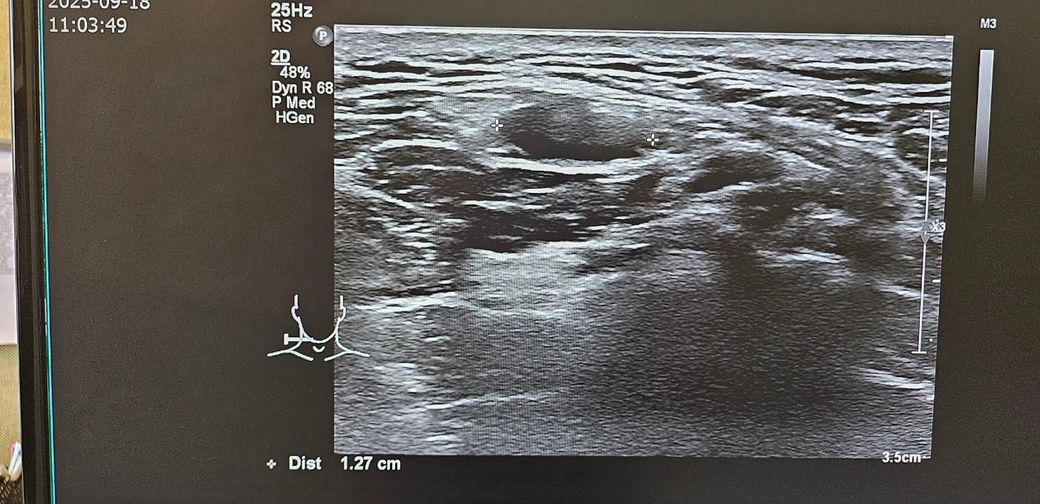

경부초음파 자세하게 설명좀 부탁드립니다

통증이있어서 초음파했는데

약먹고 통증은 없습니다

초음파 보시고 자세히 설명좀 부탁드립니다..

걱정이됩니다..부탁드립니다